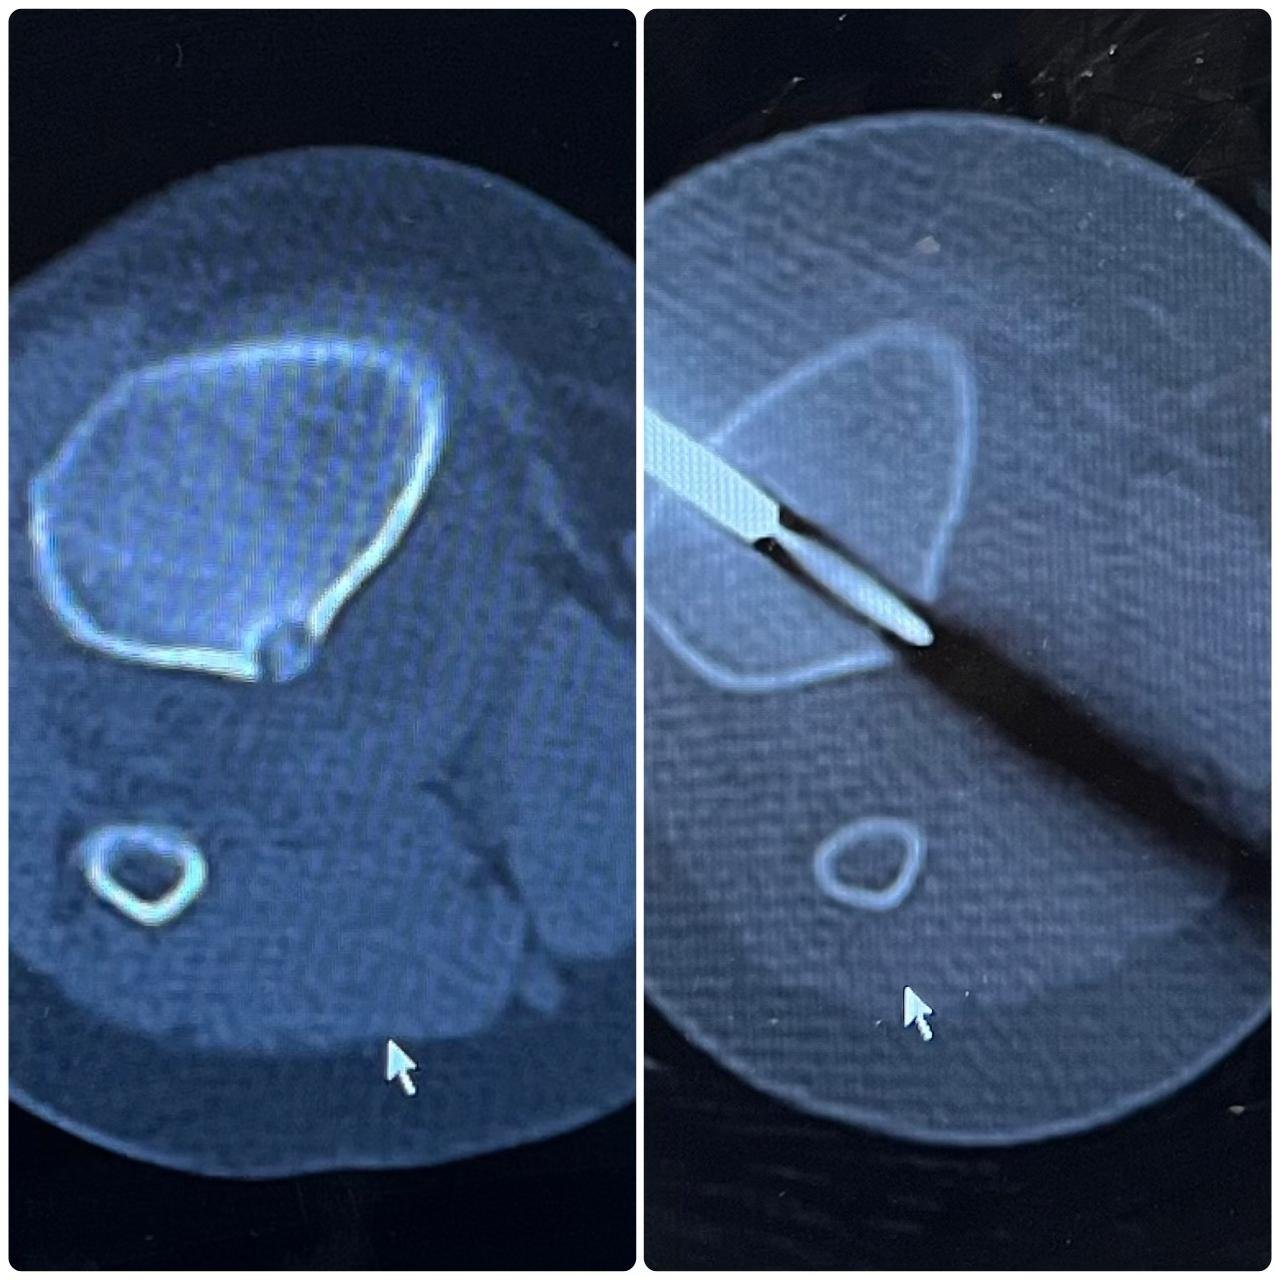

Neurovascular & Other Procedures: Osteoid Osteoma Ablations, Neurovascular Interventions